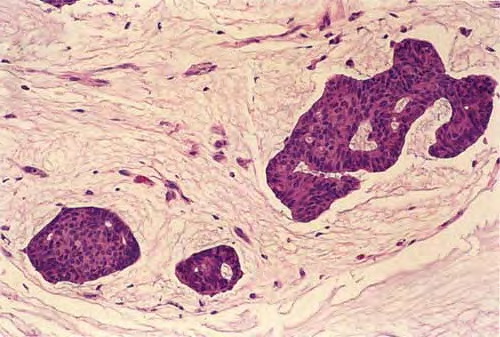

There are solid and cystic aggregations of neoplastic cells within the dermis, often with extension to the subcutis, embedded in large pools of mucin. Mucinous areas are typically separated by fibrous septae.